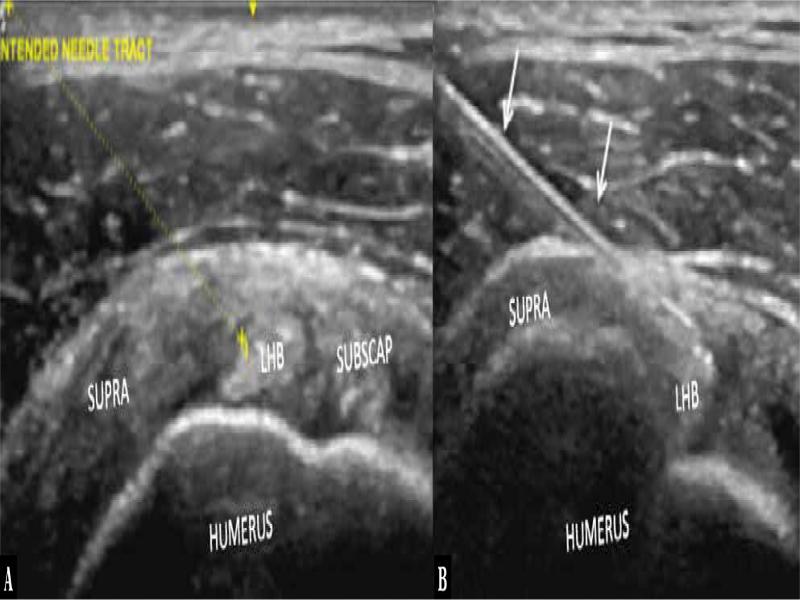

Fig. 2.

Axial ultrasound showing the indented trajectory of the needle ( A ) with a needle tip in the target zone ( B ) via lateral to medial approach